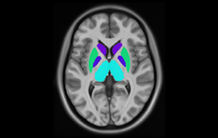

NeuroSpin, dirigé par Cyril Poupon, est un centre de recherche pour l'innovation en imagerie cérébrale situé sur le site du CEA Paris-Saclay. A NeuroSpin, physiciens, mathématiciens, neuroscientifiques et médecins s'allient pour développer en synergie les outils et les modèles qui permettront de mieux comprendre le fonctionnement du cerveau normal et pathologique, avant ou après traitement. Centrées sur la neuroimagerie, les recherches conduites vont des développements technologiques et méthodologiques (acquisition et traitement des données) aux neurosciences précliniques et cliniques, incluant les neurosciences cognitives.

NeuroSpin comporte quatre unités de recherche implantées sur le site de Saclay et une unité située à Bordeaux :

• Unité Mixte de Recherche, BAOBAB (Building large instruments for neuroimaging: from population imaging to ultra-high magnetic fields), sous tutelle CEA, CNRS et Université Paris Saclay​​ ;

responsable : Jean-François Mangin ;

• Unité mixte de recherche en Neuroimagerie Cognitive, UNICOG (U992), sous tutelle CEA, Inserm et Université Paris-Saclay ;

responsable : Stanislas Dehaene ;

• Unité de recherche en NeuroImagerie Applicative Clinique et Translationnelle (UNIACT), rattachée à l'UMR 1141 ;

responsable : David Germanaud ;

• Unité mixte MIND (Models and Inference for Neuroimaging Data, ex-PARIETAL), sous tutelle Inria et CEA;

responsable : Philippe Ciuciu ;

• Groupe d'Imagerie Neurofonctionnelle (GIN-IMN), situé à Bordeaux et rattaché à l'UMR 5293 ;

responsable : Fabrice Crivello.